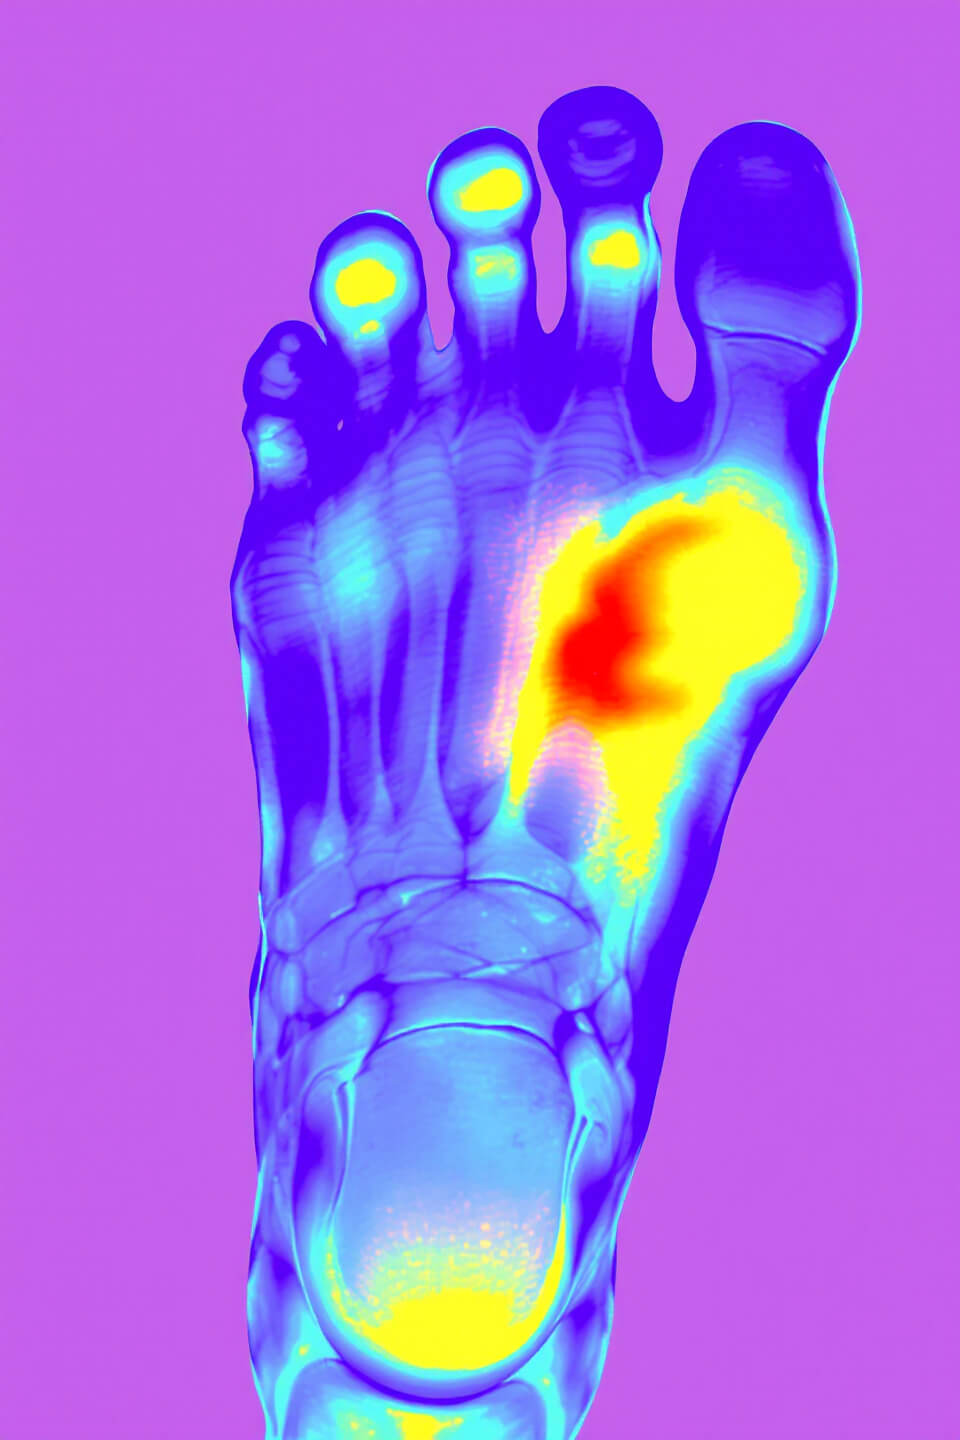

2. 통풍 초기증상 🦶🔥

✅ 1) 엄지발가락 관절 통증

- 통풍은 엄지발가락 관절(엄지발가락 관절염)에서 가장 흔하게 발생합니다.

- 갑자기 엄지발가락이 욱신거리고 심한 통증이 나타나며, 붓고 열감이 동반됩니다.

✅ 3) 관절 부위 붓기 및 발적(붉어짐)

- 통풍이 발생한 부위는 심하게 붓고, 피부가 붉어지거나 보라색으로 변색될 수 있습니다.

- 붓기가 심해지면서 신발을 신기 어려울 정도로 커질 수도 있습니다.

✅ 4) 관절 부위 열감 및 뜨거운 느낌

- 통풍 발작이 발생하면 통증 부위가 뜨겁고 화끈거리는 느낌이 듭니다.

- 만졌을 때 열이 나며, 몸살 기운처럼 열감이 느껴질 수도 있습니다.